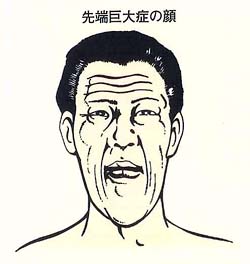

2割強の腺腫が成長ホルモンを分泌します。思春期に発症した場合は、身長や手足が異常に伸びいわゆる巨人症となります。

一方、成長してから発症した場合は、先端巨大症となります。これは手足の先端、額、あご、くちびる、舌等が肥大することで指輪やクツのサイズが合わなくなってきます。そのため顔つきは数年間でかなりかわってしまいます。成長ホルモンが長期間異常値を示していると、糖尿病、心不全、動脈硬化症や直腸癌等を合併し寿命が短くなります。